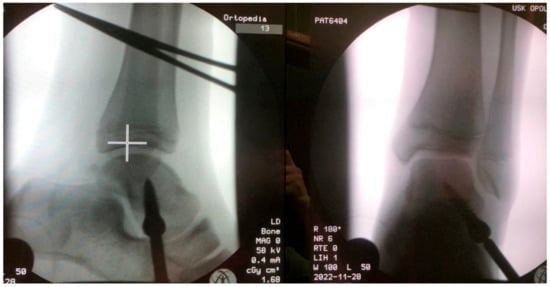

This study involved a prospective assessment of patients treated surgically for symptomatic flexible flatfoot deformity in the period 2021–2022. The study inclusion criteria were symptomatic flexible flatfoot, treatment via arthroereisis with the Spherus talar screw (Gruppo Bioimpianti S.R.L., Milan, Italy), age 7–14 years, informed assent, complete medical and radiological records, and a follow-up period of at least 12 months. The diagnosis of symptomatic flexible pes planovalgus was corroborated by the patient’s history, clinical examination, and radiological imaging. All evaluated patients had received conservative treatment, including rehabilitation and shoe inserts. All patients exhibited hindfoot eversion and medial longitudinal arch collapse and experienced foot pain and problems with gait. Study exclusion criteria were other lower limb pathologies (such as cerebral palsy, tarsal coalition, other foot deformities, or rheumatoid joint disease), history of foot surgery, neurological conditions, history of foot injuries, incomplete medical or radiological records, a lack of informed assent, or a follow-up period shorter than 12 months. This study was approved by the local ethics committee. All patients and their legal guardians were informed of the voluntary nature of their participation in this study. Thirty-five arthroereisis procedures with the use of the Spherus talar screw were conducted in our center in the years 2021 and 2022, Figure 1.

Figure 1. Radiologic images after pes planovalgus correction with the Spherus screw.